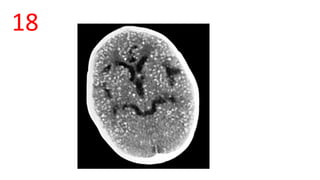

18

19

Huntington disease

Box-Car ventricle sign

• caudate nuclei are partially atrophied with

enlargement of the frontal horns

• The intercaudate distance to inner table

ratio (CC:IT) is increased (N = 0.9-1.2)

• frontal horn width to intercaudate

ratio (FH:CC) is decreased (N = 2.2-2.6 ).